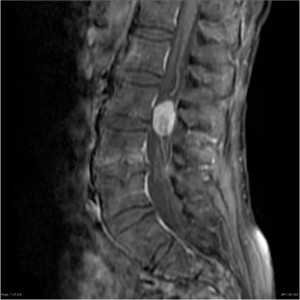

Изменения сигнала по типу MCh3 встречаются наименее часто и характеризуются гипоинтенсивным сигналом на T1- и Т2-ВИ на МРТ (рис. 3) [10]. Гистологически этот тип не изучался. На микро-КТ выявляются изменения, связанные с повышением уровня образования костной ткани и снижением ее резорбции [11]. На изображениях, полученных при проведении рентгенографии и мультиспиральной компьютерной томографии (МСКТ), этот тип характеризуется значительным уплотнением костной ткани — остеосклерозом [19, 20].

Рис. 3. Изменения на МРТ по типу MCh3. 1 — гипоинтенсивный сигнал на T1-ВИ; 2 — гипоинтенсивный сигнал на Т2-ВИ.